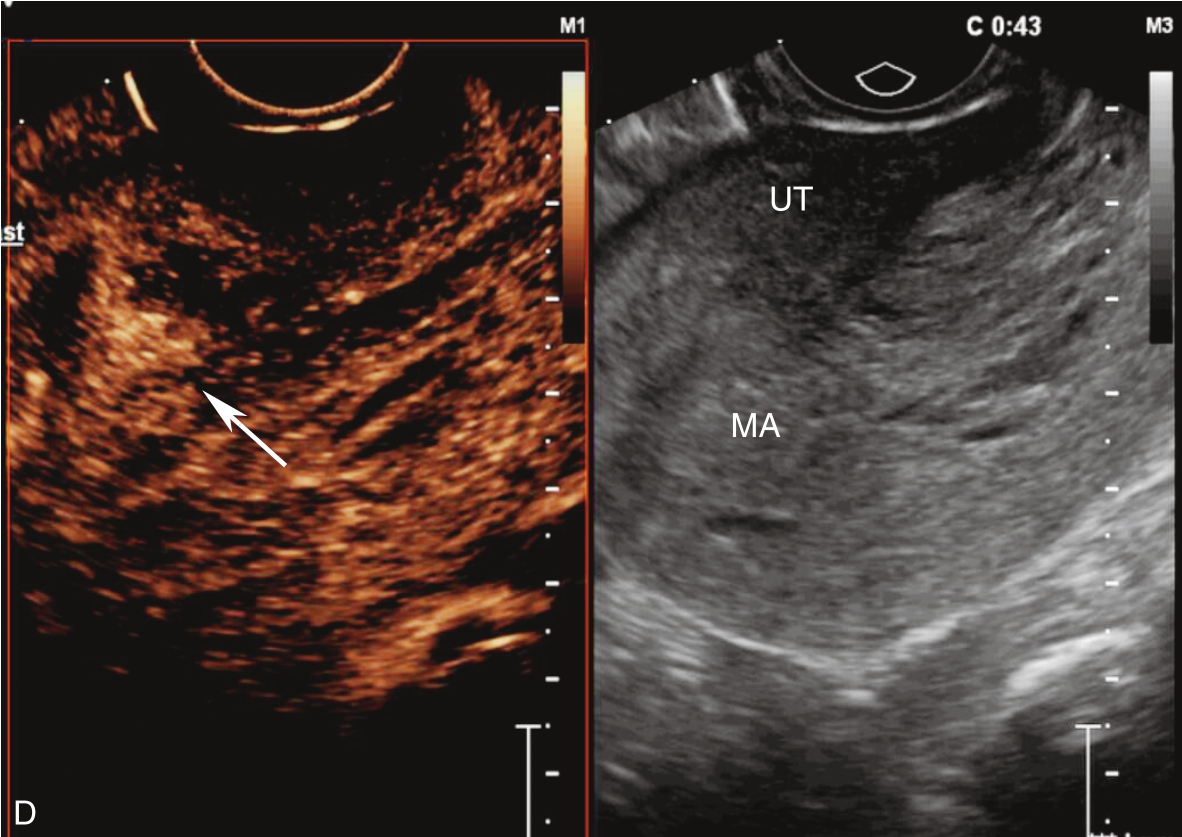

经静脉超声造影见图3-10-2及ER 3-10-1。注入造影剂后11s,宫腔内不均质稍强回声团块开始出现增强(图3-10-2A箭头所示),稍早于子宫肌层增强;注入造影剂后22s,团块根蒂似附着于宫腔上段宫底处(图3-10-2B箭头所示);注入造影剂后26s,宫腔内团块呈高增强,且其内造影剂分布不均匀(图3-10-2C箭头所示);注入造影剂后43s,宫腔内团块造影剂消退晚于子宫肌层(图3-10-2D箭头所示)。

图3-10-2 经静脉超声造影声像图

A.注入造影剂后11s;B.注入造影剂后22s;C.注入造影剂后26s;D.注入造影剂后43s。UT:子宫;MA:肿物。